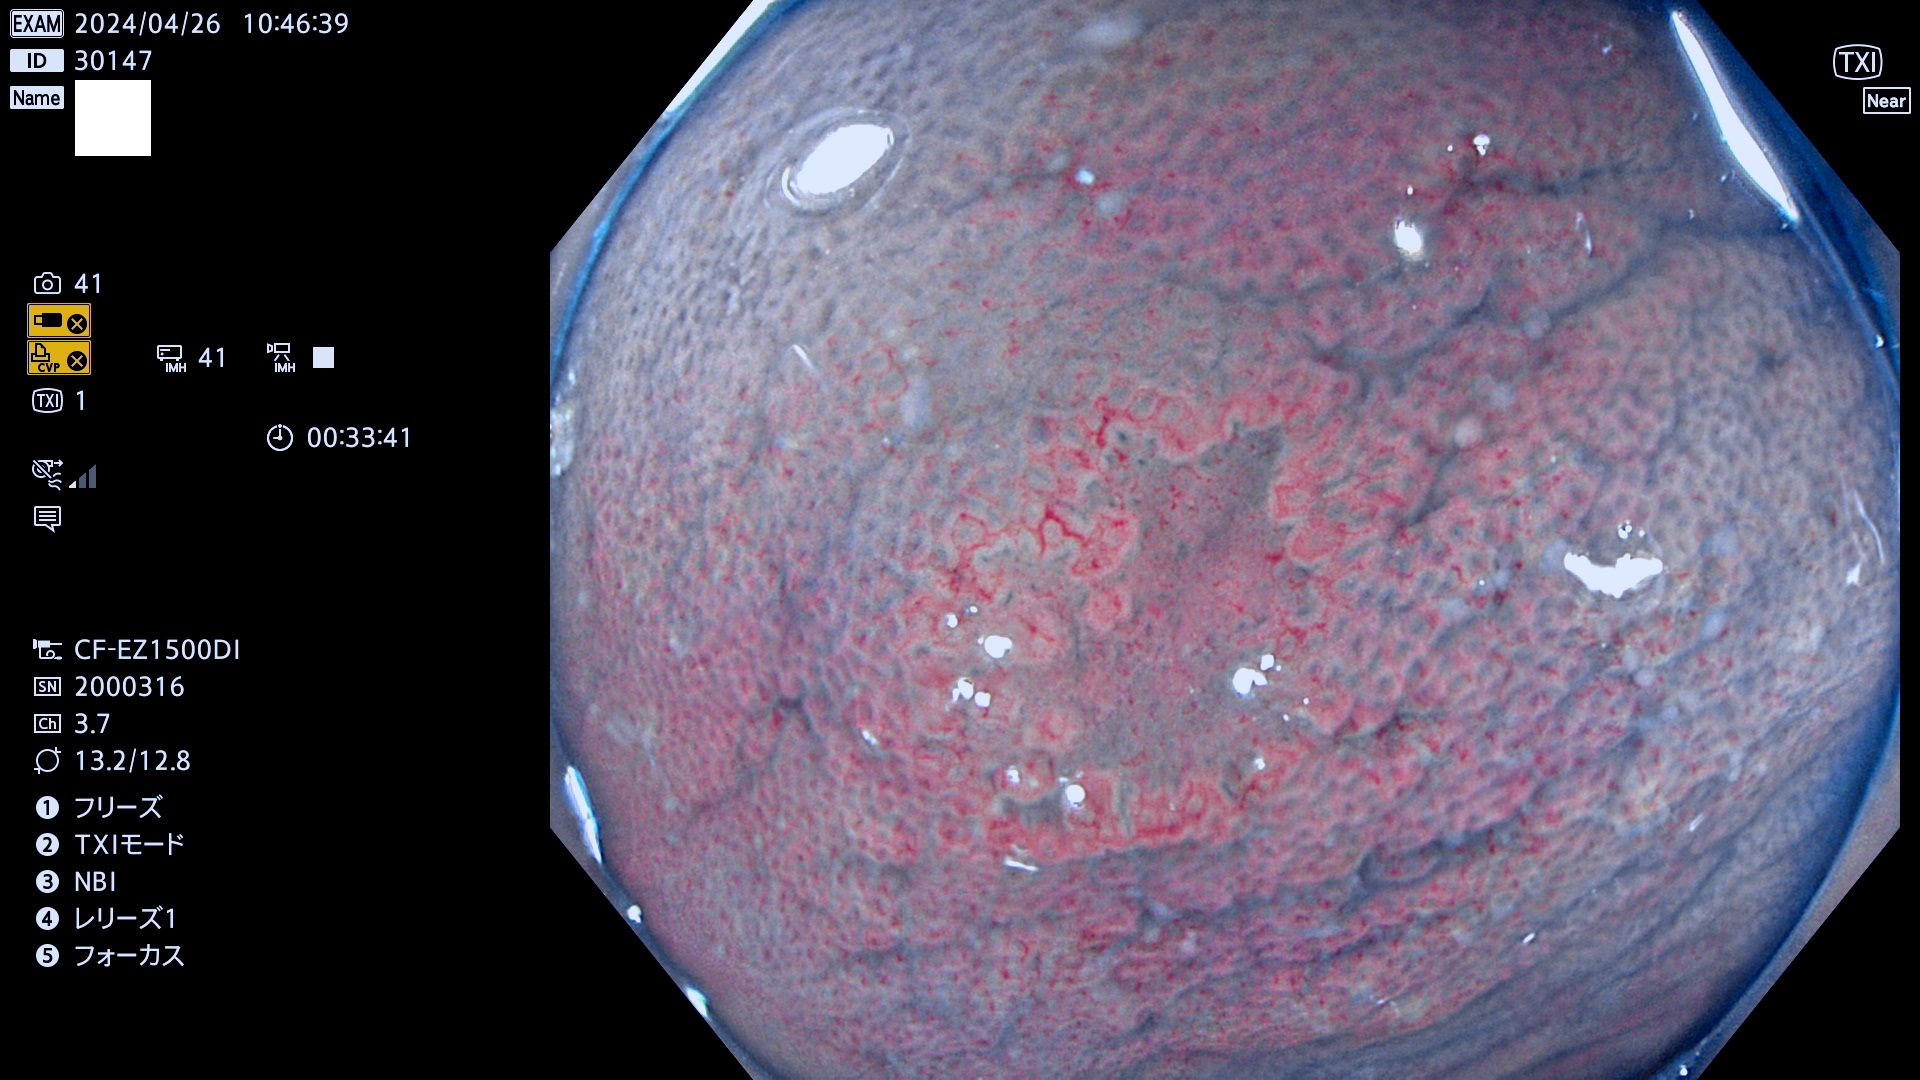

表面型腺腫(Flat Adenoma)の中で、完全に平坦な物をUb、陥凹している物をUcと呼びます。平坦隆起型(Ua)よりも、発見が難しく危険な病変です。

専門的)何故、陥凹していると危険? 癌遺伝子の変異が蓄積すると細胞分裂が盛んになり隆起するのでは?と通常は思われるでしょう。しかし実際は逆です。これは2022年の記事にある「細胞はストレスに直面したら細胞分裂を止める(細胞老化に入り休眠する)という生命の基本的現象」によるものです(Oncogene Stress)。細胞老化を起こすのが癌抑制遺伝子で、この安全装置(ブレーキ)が壊れると癌になります(休眠からの覚醒)。ですから陥凹は「まだ癌では無いが癌化の直前」を意味します。特に「小サイズなのに陥凹している」病変は短期間に腫瘍進化(IntraTumor Heterogenity⇒2021年記事)が起きたことを意味します(=ゲノム不安定性

抽出の対象期間 2024年4月25日〜4月29の5日間(50件の検査)7件 (7/50=14%)